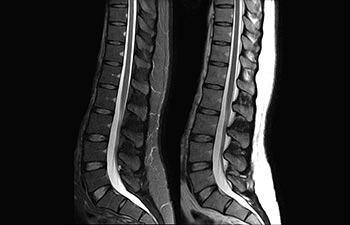

1 In base a uno studio interno in cui si confronta il flusso di lavoro con il sistema RM Achieva. 2 ComforTone sarà disponibile con Prodiva 1.5T a partire da fine 2017. 3 In base a uno studio interno che ha confrontato il flusso di lavoro di una serie di applicazioni su cervello, colonna vertebrale, apparato muscoloscheletrico e corpo con il sistema RM Achieva. 4 Per normale funzionamento si intende una scansione tipica eseguita in condizioni di disponibilità ininterrotta di elettricità, con raffreddamento del magnete e senza interventi di assistenza. 5 A seconda di quanto previsto nel contratto e della disponibilità locale. 6 "Altri" si riferisce a sistemi RM 1.5T da 60 cm per il corpo intero